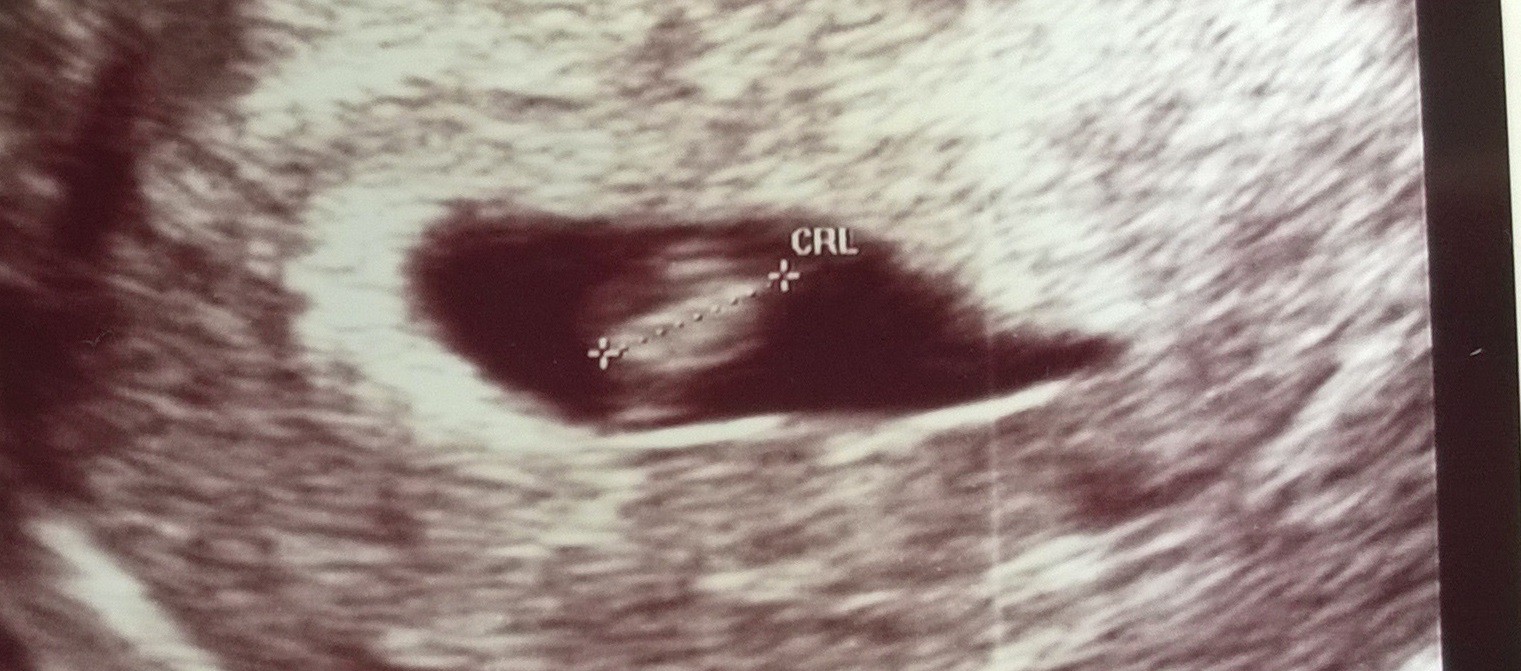

Fanka BB :)

Lux Ja czułam dziewczynkę ale teraz juz nie wiem bo bardzo wyladnialam a mówią ze to na chłopca

ważne żeby zdrowe a będę się cieszyć z córki jak i syna